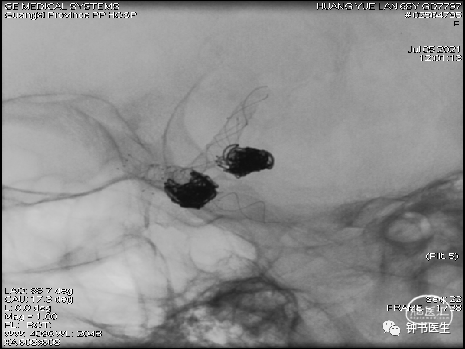

2021-07-05 DSA

Tubridge 4045

TB植入后动脉瘤即刻不显影。